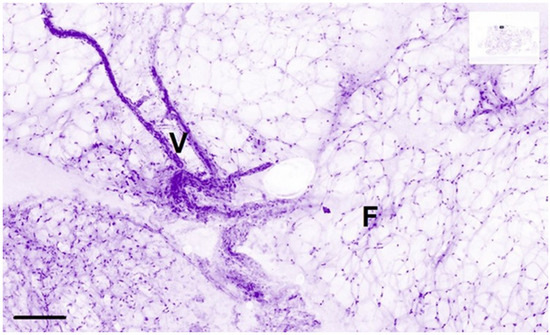

- Mathieu, M.; Ragazzi, M.; Van Diest, P.; Ferchiou, M.; Casiraghi, O.; Labaied, N.; Conversano, A.; Abbaci, M. Atlas of ex vivo breast tissue and carcinomas images by ultra-fast large feld-of-view fuorescence confocal microscopy of lumpectomy. Virchows Arch. 2023, 483 (Suppl. S1), S63. [Google Scholar]